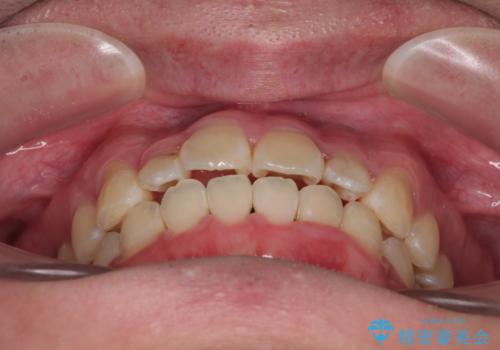

- 「歯並びがデコボコしていて、上下の中心がズレているのが気になる…」という悩みで来院された患者さまの症例をご紹介します。

初診時の状態

・上下ともに歯がきれいに並びきらず、がたつきが見られました。

・上下の前歯の中心(正中)がずれています。

・特に上顎の幅が狭いため、下顎の歯列も内側に入り込み、歯が並ぶスペースが不足していました。